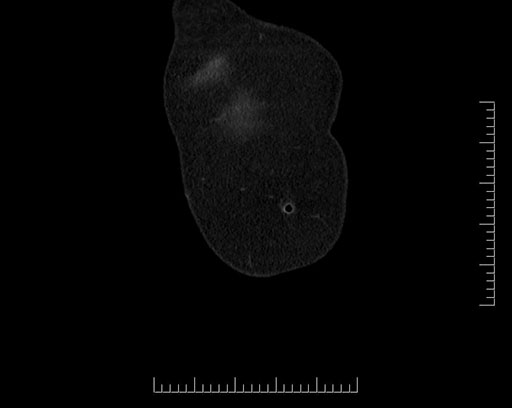

Imaging Analysis

Look through the patient's CT scan to identify any areas of concern for the necessary procedure.

Based on your CT findings, which issue(s) would give reason for "planned slowing down moment(s)" in this case?